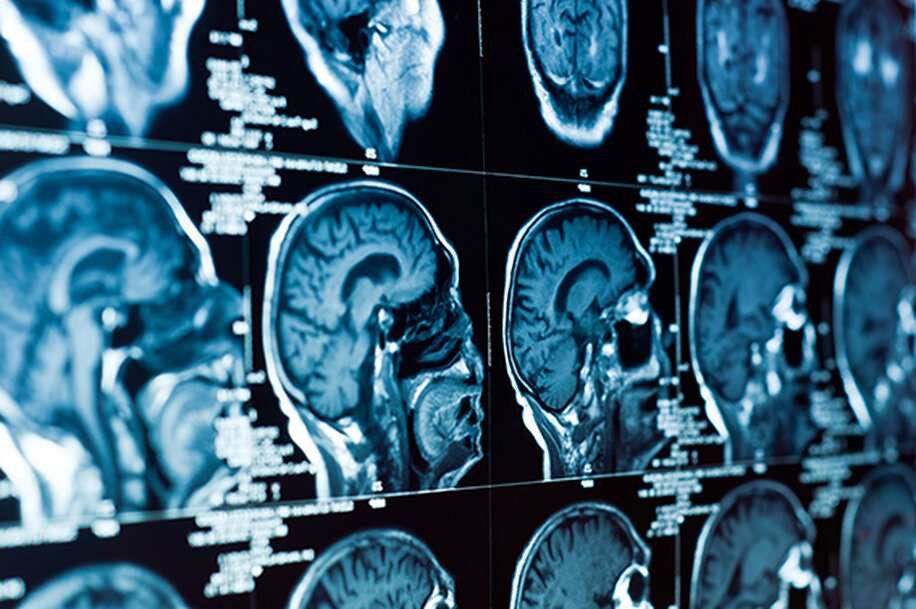

• 02.

Medical imaging analysis

Detecting relevant issues and presenting them to radiologists in a friendly summary view enables the design of more customized, targeted and accurate report used in diagnostic decision process.teeth